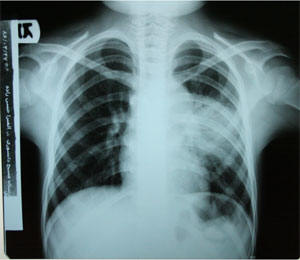

Radiological findings

CXR= Mass

Consolidation in left parahilar region with adenopathy in same side.

Lung CT-scan=

Consolidation in anterior segment of LUL with left parahilar lymphadenopathy and

mediastinal calcification.